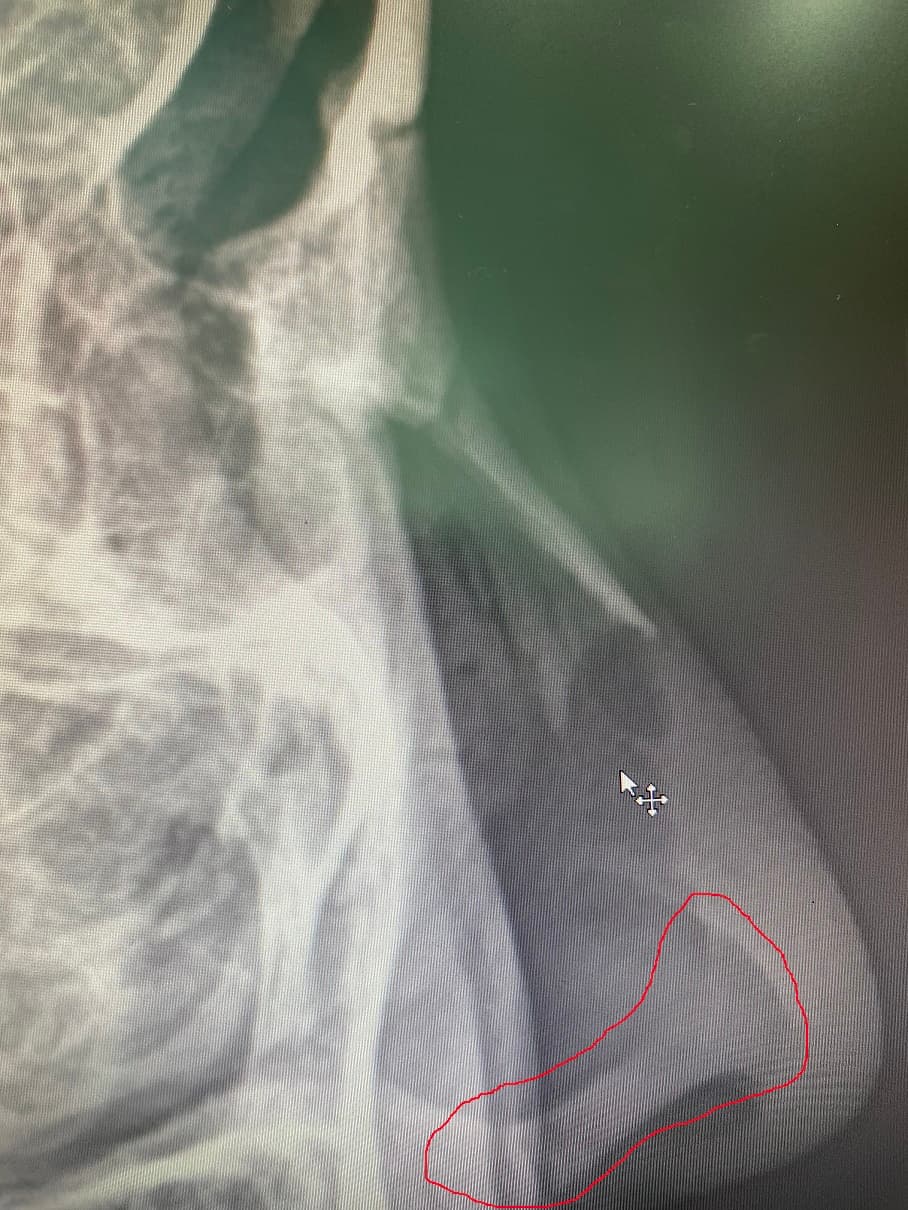

사진에서 제가 빨간색으로 표시한 부분이요. 콧구멍 바로 위에 하얗게 보이는 부분요.

코중격 연골인 것으로 판단됩니다. /////////////////////////